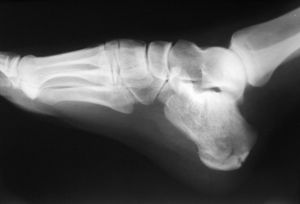

4. 임상적 의의

정상적인 경우 정강뼈는 발꿈치뼈 위 수직으로 위치한다(''pes rectus''). 이 두 뼈 사이의 발꿈치뼈 축이 안쪽으로 회전하면 발은 외반(''pes valgus'')되고, 바깥쪽으로 회전하면 내반(''pes varus'')된다.[5]

4. 1. 발꿈치뼈 골절

발꿈치뼈 골절은 '연인 골절' 및 '돈 후안 골절'로도 알려져 있다.

4. 2. 질병

족근골 유합의 경우 일반적으로 발꿈치뼈 선반이 관여한다.참조